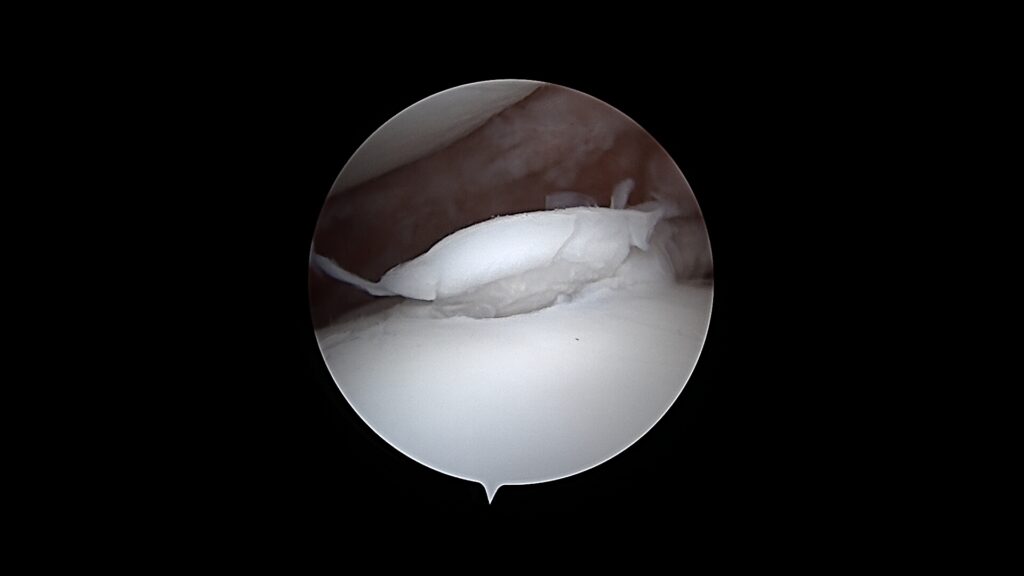

L’arthroscopie du genou est utilisée à la Clinique Sirius à des fins diagnostiques et thérapeutiques, notamment dans le cadre des affections du ligament croisé crânial. Elle permet d’explorer l’intérieur de l’articulation du genou, d’évaluer l’état du ligament croisé, des ménisques et du cartilage articulaire.

Sur le plan diagnostique, l’arthroscopie permet de confirmer la rupture partielle ou complète du ligament croisé, d’apprécier les lésions associées et de poser une indication chirurgicale adaptée. Sur le plan thérapeutique, elle permet notamment le traitement des lésions méniscales, avec le retrait ciblé des lambeaux méniscaux instables, ainsi que l’élimination des débris ligamentaires intra-articulaires.

L’arthroscopie du genou peut être intégrée à une prise en charge chirurgicale plus globale, en complément des techniques de stabilisation du genou, afin d’optimiser le résultat fonctionnel à long terme.

De gauche à droite : Retrait d’un fragment de processus coronoïde interne sur le coude d’un Cane Corso. Volet d’OCD sur une épaule d’un Border Collie. Exploration du genou d’un Berger Australien : LCP = ligament croisé postérieur, LCA = ligament croisé antérieur.